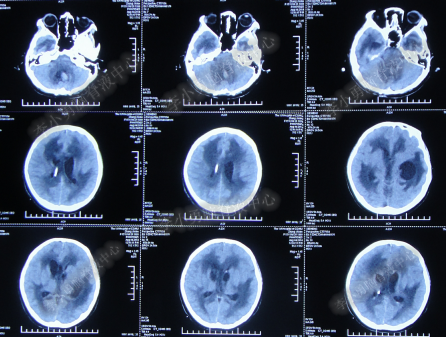

腰大池持续引流20天内,体温仍间断高热,曾3次脑脊液细菌培养均示鲍曼不动杆菌,先后使用利奈唑胺+克倍宁,利奈唑胺+克倍宁+奥硝唑,舒普深+米诺环素+来立信+氟康唑,舒普深+米诺环素+美罗培南+氟康唑,及日达仙、人免疫球蛋白提高免疫力,但颅内感染仍控制不住,期间多次头部CT检查均示脑室无明显扩张(图-7、图-8、图-9)。

图-7:2014年6月9日头部CT

图-8:2014年6月14日头部CT

图-9:2014年6月21日头部CT